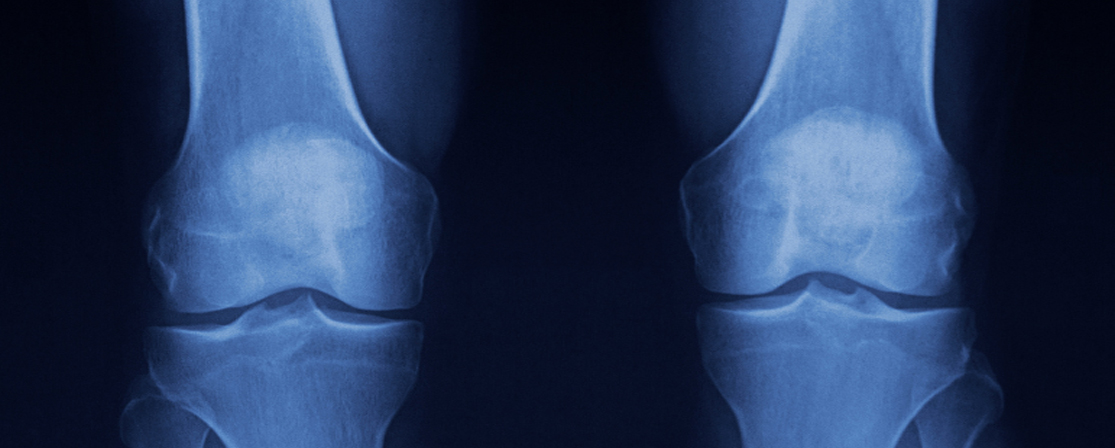

Osteoarthritis in the Knee

Knee osteoarthritis (OA) is a degenerative joint disease that occurs when the protective cartilage in the knee gradually wears down. This leads to pain, stiffness, swelling, and reduced mobility. It is one of the most common causes of knee pain, particularly in older adults.